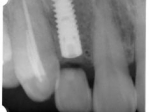

術後(レントゲン)、左下奥2本インプラント